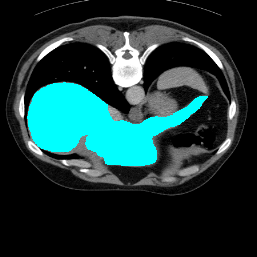

In order to assess the performance of the proposed method, we compare the performance of the proposed model with excellent models in recent years. Table 1 and Table 2 shows the comparison results of different models in setting1, while Table 3 and Table 4 shows the comparison results of different models in setting2 on the data set in recent years. PANet[25] is the most widely influential few-shot model in the field of few-shot image segmentation on natural images. SENet [18] is the first few-shot segmentation model proposed for medical images. SSL-ALPNet[19] introduced the milestone of using superpixel self-supervision to train few-shot medical image models. RPNet[29] is a supervised method with a recursive mask optimization module to iteratively optimize the segmentation mask, [27] adapt it into the same self-supervision learning framework and applies setting1 to it and denoted as SSL-RPNet; CRAPNet[27] is the latest SOTA model for 2023. Compared with CRAPNet, our method outperforms most of the state-of-the-art models and only slightly outperforms CRAPNet. Figures 3 and 4 show examples of the model’s segmentation predictions on different datasets, respectively; The first row is the support map, the second row is the label map, and the third row is the segmentation prediction of the model.